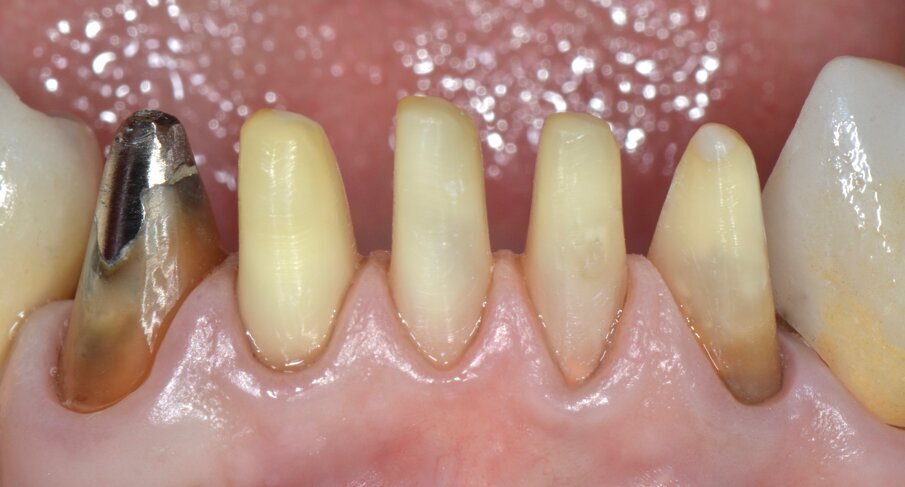

Riguardo al comparto intraorale, dalle radiografie diagnostiche e dall’esame parodontale e occlusale sono emersi aspetti che meritavano una correzione anche nei settori posteriori, ma la paziente ha deciso di effettuare inizialmente il trattamento dei soli gruppi frontali superiore e inferiore demandando a un momento successivo le problematiche dei quadranti posteriori (Figg. 2-6). Nel gruppo frontale superiore si possono notare recessioni gengivali sugli incisivi centrali, che sono anche molto ruotati, e sul canino di sinistra; corone in metallo-ceramica sugli incisivi laterali con esposizione del bordino metallico e una corona in ceramica metal-free sul canino di destra. Inoltre è molto evidente lo squilibrio delle parabole gengivali tra i due canini, per cui per ristabilire un’estetica ottimale sarà necessario anche interessare i tessuti molli eseguendo una chirurgia resettiva sul canino di destra e, al contrario, un lembo a posizionamento coronale sul canino di sinistra (Fig. 7).

Da un punto di vista protesico verranno eseguite corone singole in zirconia stratificata sugli elementi 13-12-11-21-22 e una faccetta in disilicato di litio sul 23. A causa della notevole rotazione dei due incisivi centrali in fase di ceratura abbiamo optato per due corone complete anziché due faccette per una migliore distribuzione degli spazi protesici dei quattro incisivi (Fig. 8). Il gruppo frontale inferiore invece verrà protesizzato con corone in zirconia stratificata sugli elementi 32-31-41-42-43 splintate per compensare una mobilità di grado 1 dei quattro incisivi.